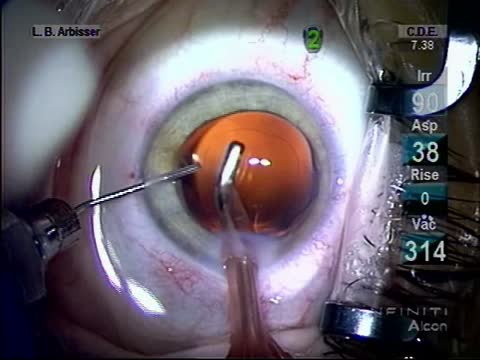

Iris Prolapse

Lisa Brothers Arbisser, MD